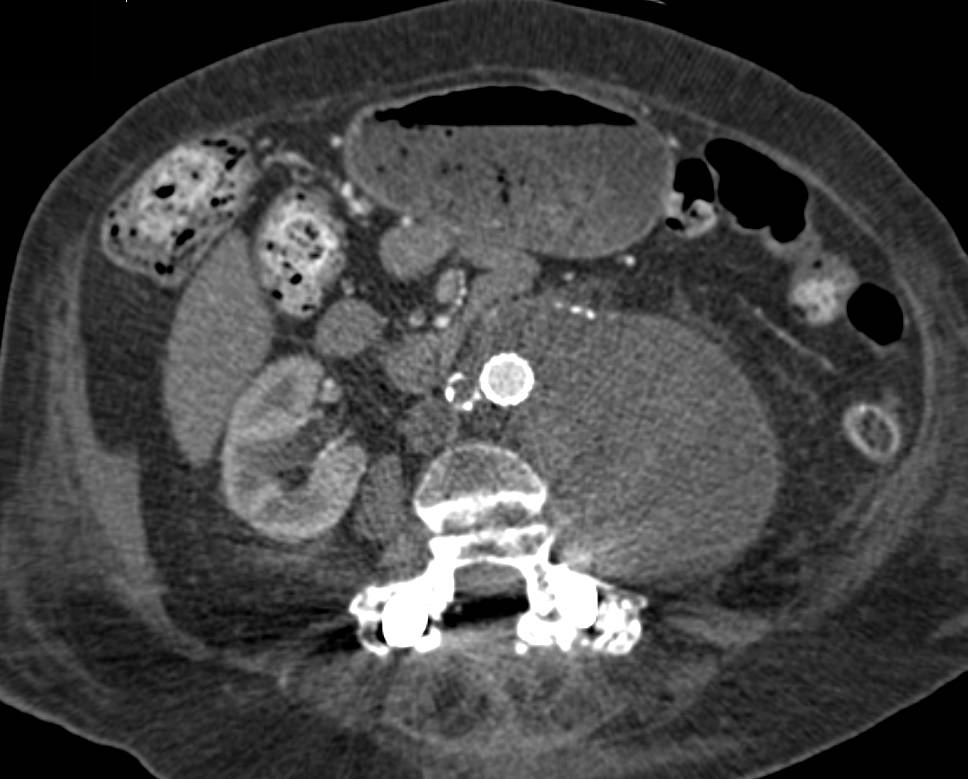

Diagnosis

Dilated Main Pulmonary Artery due to Pulmonary Hypertension